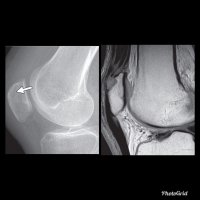

A Tillaux fracture is a traumatic Salter–Harris type III fracture through the anterolateral aspect of the distal tibial epiphysis, with variable amounts of displacement.

It accounts for 3-5% of pediatric ankle fractures and more commonly seen in girls. Tillaux feacture is seen in children nearing skeletal maturity (12-14 years old), when the medial epiphysis had closed but before the lateral side has done so.

The fracture commonly results from an abduction-external rotation force, causing the anterior tibiofibular ligament to avulse the anterolateral corner of the distal tibial epiphysis, at the opposite end to a Wagstaffe-Le Fort avulsion fracture, resulting in a Salter Harris Type III fracture.

Variability in fracture pattern is due to progression of physeal closure as anterolateral part of distal tibial physis is the last to close. When the lateral physis is the only portion not fused, external rotation may lead to Tillaux or Triplane fractures. Lack of coronal plane fracture in the posterior distal tibial metaphysis distinguishes this fracture from a triplane fracture.

Associated conditions commonly seen with this fracture are distal fibular fracture (usually SH I or II) and ipsilateral tibial shaft fracture.

If the displacement at fracture is less than 2 mm, it may be managed conservatively. However, displacement requires open reduction and internal fixation, especially when displacement is over 2 mm.

As with any intra-articular fracture if a step is left in the articular surface, then the joint will go on to premature secondary osteoarthritis.

This fracture pattern is named after Paul Jules Tillaux, a French Anatomist and Surgeon (1834-1904).